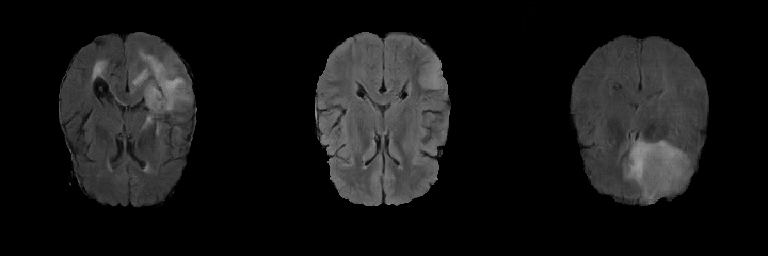

Generated Images Figure 5 shows the generated brain tumor FLAIR samples from -GAN-GP, PGGAN, and PGGAN-SSIM in AXI. The generated samples from all models look realistic and are close to the real images, where the white areas (Gliomas area) are concentrated and unified, indicating the training stability with gradient penalty. However, the samples from -GAN-GP are blurry, and the detailed brain features disappear since the loss of image information becomes serious when the image resolution increases in -GAN-GP. The generated samples from PGGAN and PGGAN-SSIM have clear and realistic brain features (FLAIR texture and tumor appearance) with diversity, which illustrates that PGGAN architecture is a well-suited model to generate brain MR images.